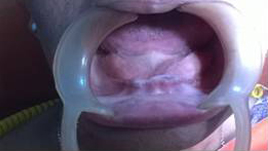

Pre Operation

Use of Bone Graft & GTR membrane for an Implant

After 6 months

Before Placement of Prosthesis